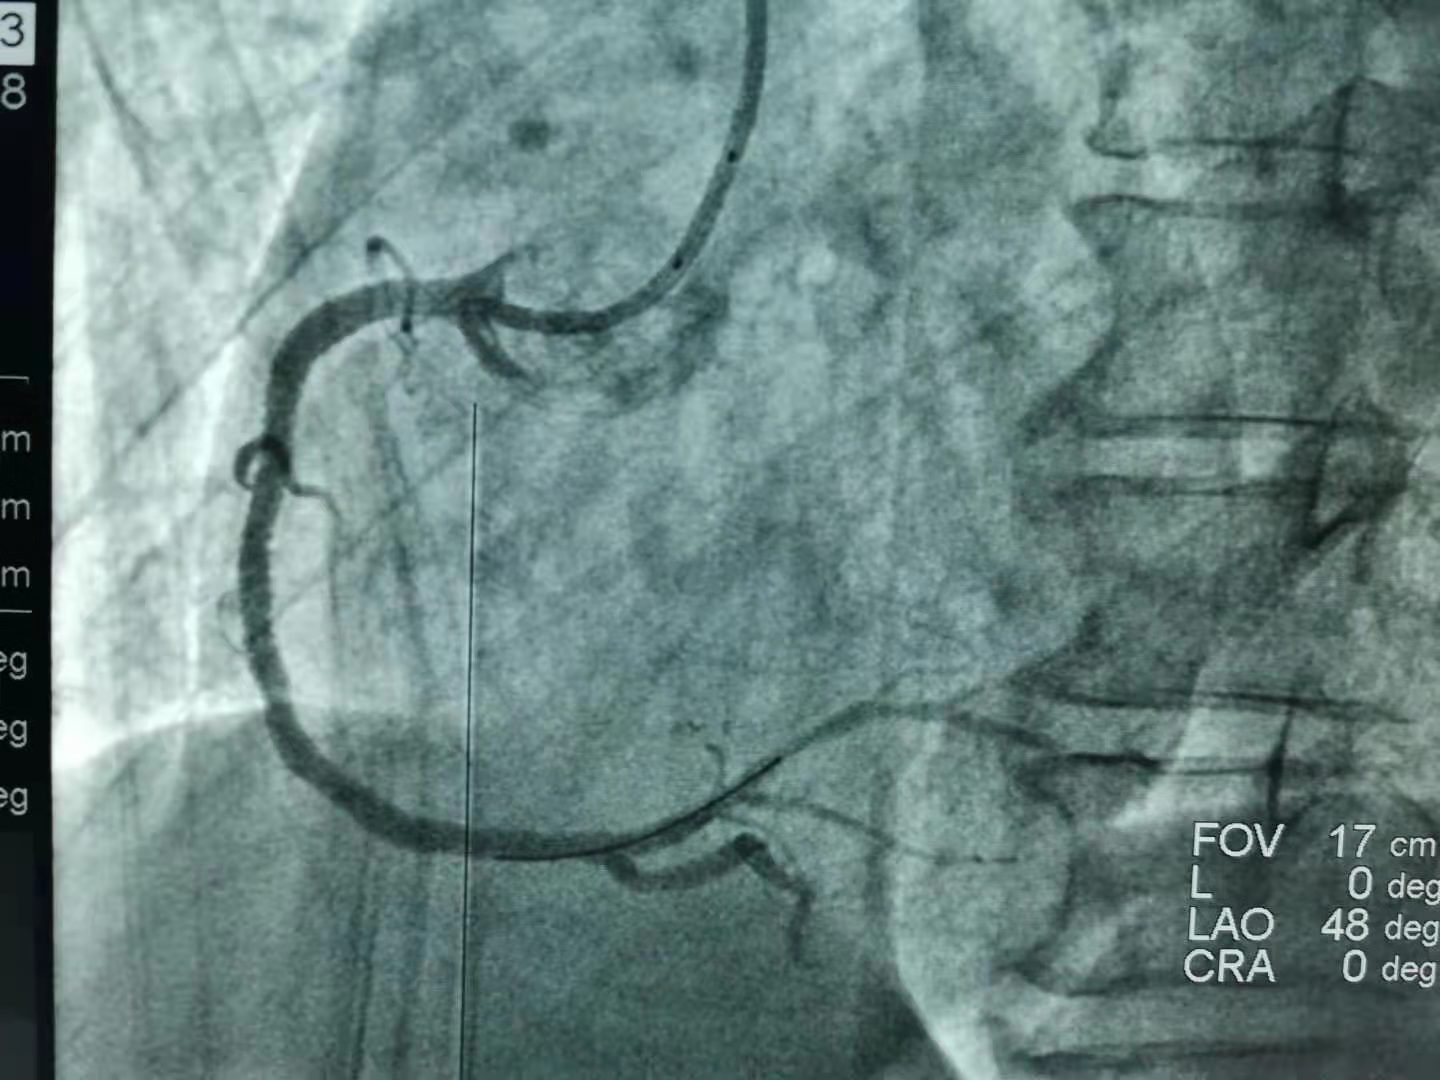

18:20“一键启动导管室”!18:35李先生到达导管室开始手术。“冠状动脉造影显示,李先生右冠状动脉近端99%的严重狭窄,需要立即植入支架!”在介绍救治方案并征得家属的同意后,副院长张施明带领胸痛中心手术团队对患者进行支架植入手术,18:53导丝通过,19:08 在距离李先生发病68分钟后,手术顺利完成,李先生转危为安。

李先生的术前术后对比,可见右冠状动脉严重狭窄处已再通,冠状动脉粗壮可见